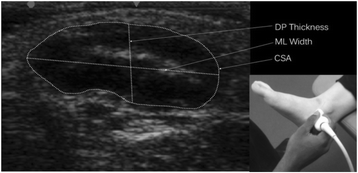

Image J v. 1.45 (National Institutes of Health, Bethesda, MD, USA), an image processing and analysis software, was used to obtain measurements for dorso-plantar thickness (mm), medio-lateral width (mm), cross-sectional area (mm2) and echo-intensity of the abductor hallucis muscle. To ensure researcher blinding, all de-identified images were randomised prior to analysis. The edges of the muscle were defined as the point between the muscle tissue and the muscle fascia (Fig. 1). The dorso-plantar thickness and medio-lateral width were determined using a line selection tool to measure the distance between the respective muscle edges. Cross-sectional area was measured manually using an area selection tool to trace around the muscle border. Echo-intensity of the cross-sectional area was measured using the grey scale analysis function, which was expressed as a value between 0 (black) and 255 (white). A higher value was interpreted as the presence of a higher quantity of intra-muscular adipose and fibrous tissue [9, 15].

Fig. 1

Abductor hallucis muscle size measurements with inset showing probe placement